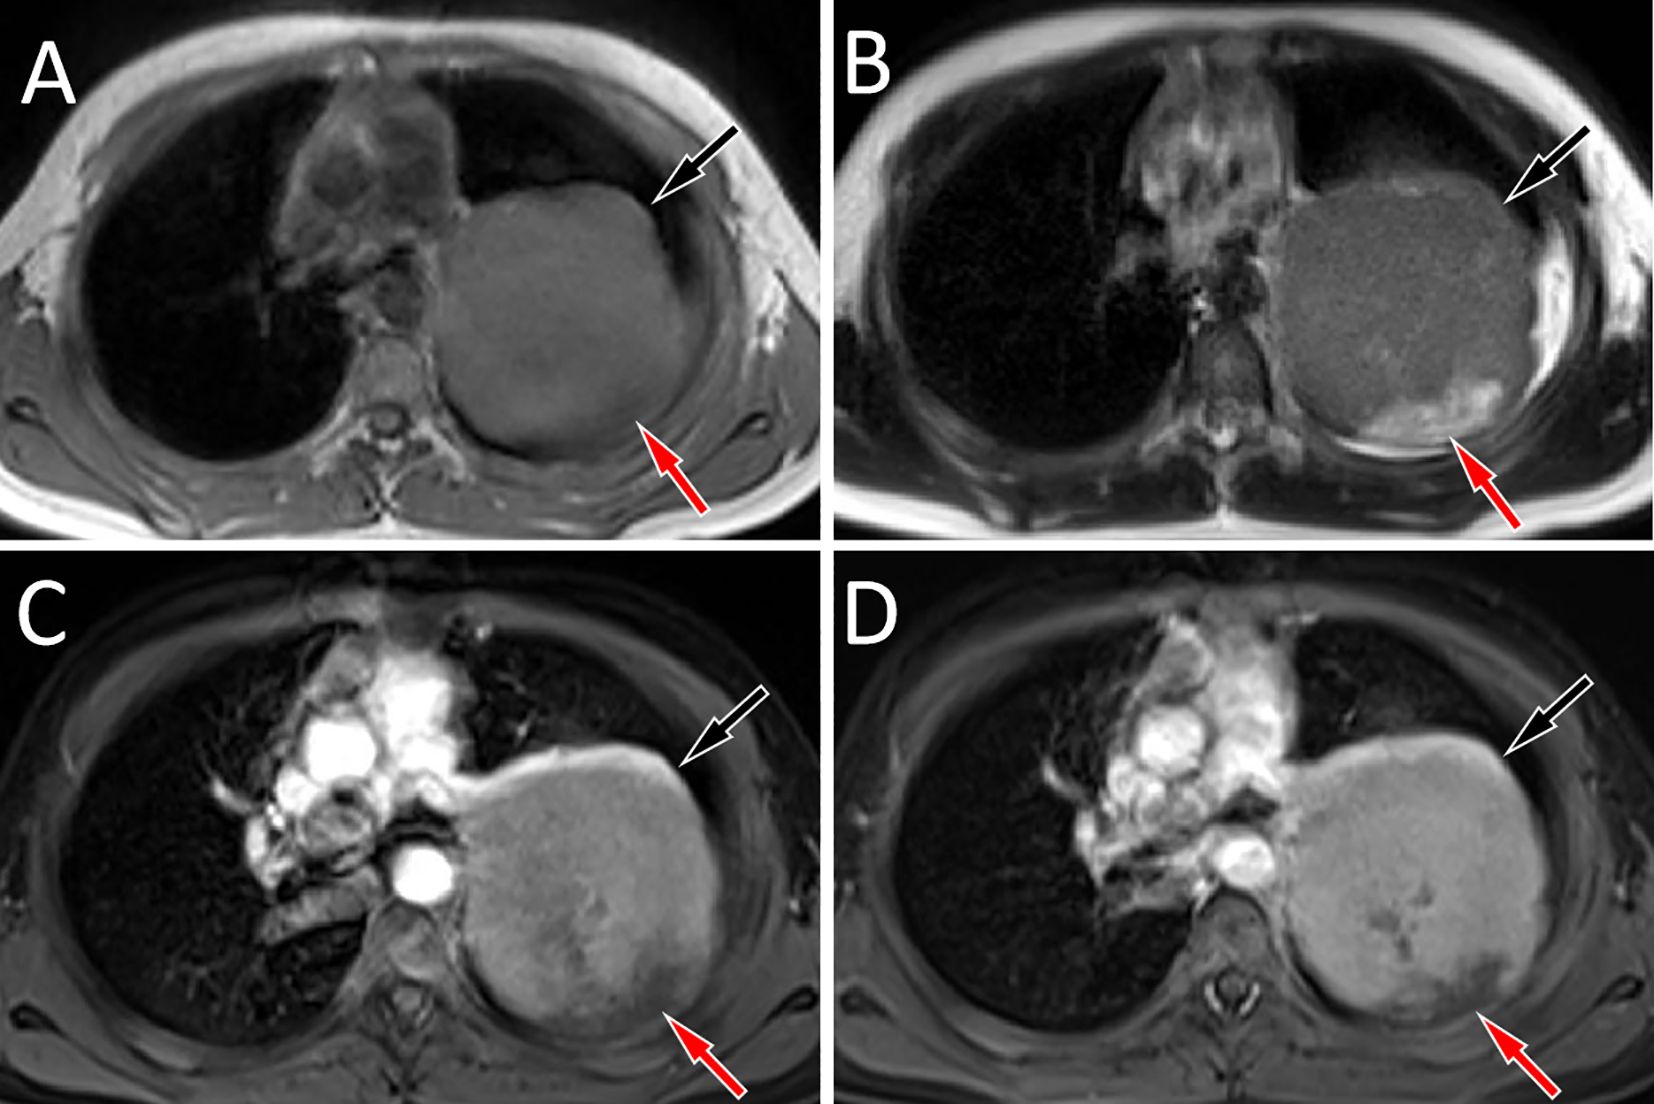

Extraskeletal Ewing sarcoma (EES) is a malignant tumor that arises in soft tissues outside the skeleton. It commonly involves the paravertebral regions, the lower extremities, and the chest wall, with mediastinal involvement being less frequent. Here, we report an 11-year-old male with pathologically confirmed EES occurring in the mediastinum. Chest computed tomography (CT) showed a large soft tissue density mass on his left posterior mediastinum, containing internal low-density cystic necrotic areas. The solid component was isointense to muscle on T1-weighted imaging (T1WI) and mildly hyperintense on T2-weighted imaging (T2WI), whereas the cystic components were hyperintense on T2WI and variably hyperintense on T1WI. On contrast-enhanced CT and T1WI, the mass demonstrated heterogeneous, progressive enhancement, suggesting the possibility of malignant tumor. A needle biopsy confirmed the diagnosis of EES. After diagnosis, the patient received systemic chemotherapy followed by surgical resection of the tumor. We also conducted a systematic review of the published literature on mediastinal EES, summarizing its clinical and imaging features, with the aim of increasing understanding of this rare disease.